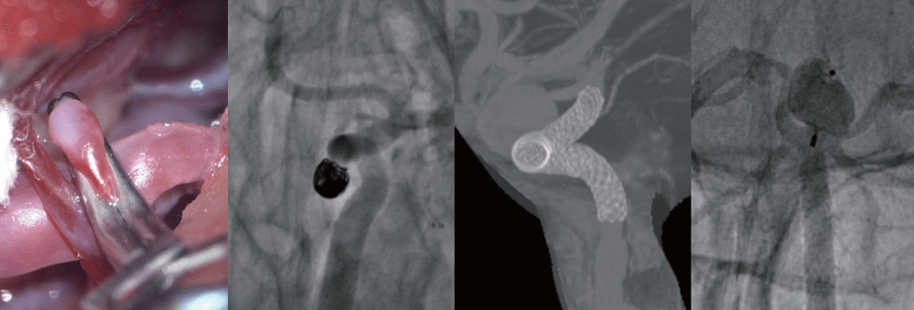

(왼쪽부터) 클립 결찰술, 코일 색전술, 혈류전환 스텐트 삽입술, 혈류차단기 삽입술